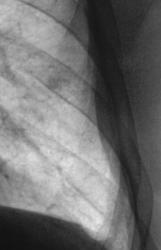

Окружающая легочная ткань - 2008 и 2009 г.

Кстати, какие-то неясные очажки вокруг. А вдруг туберкулема?